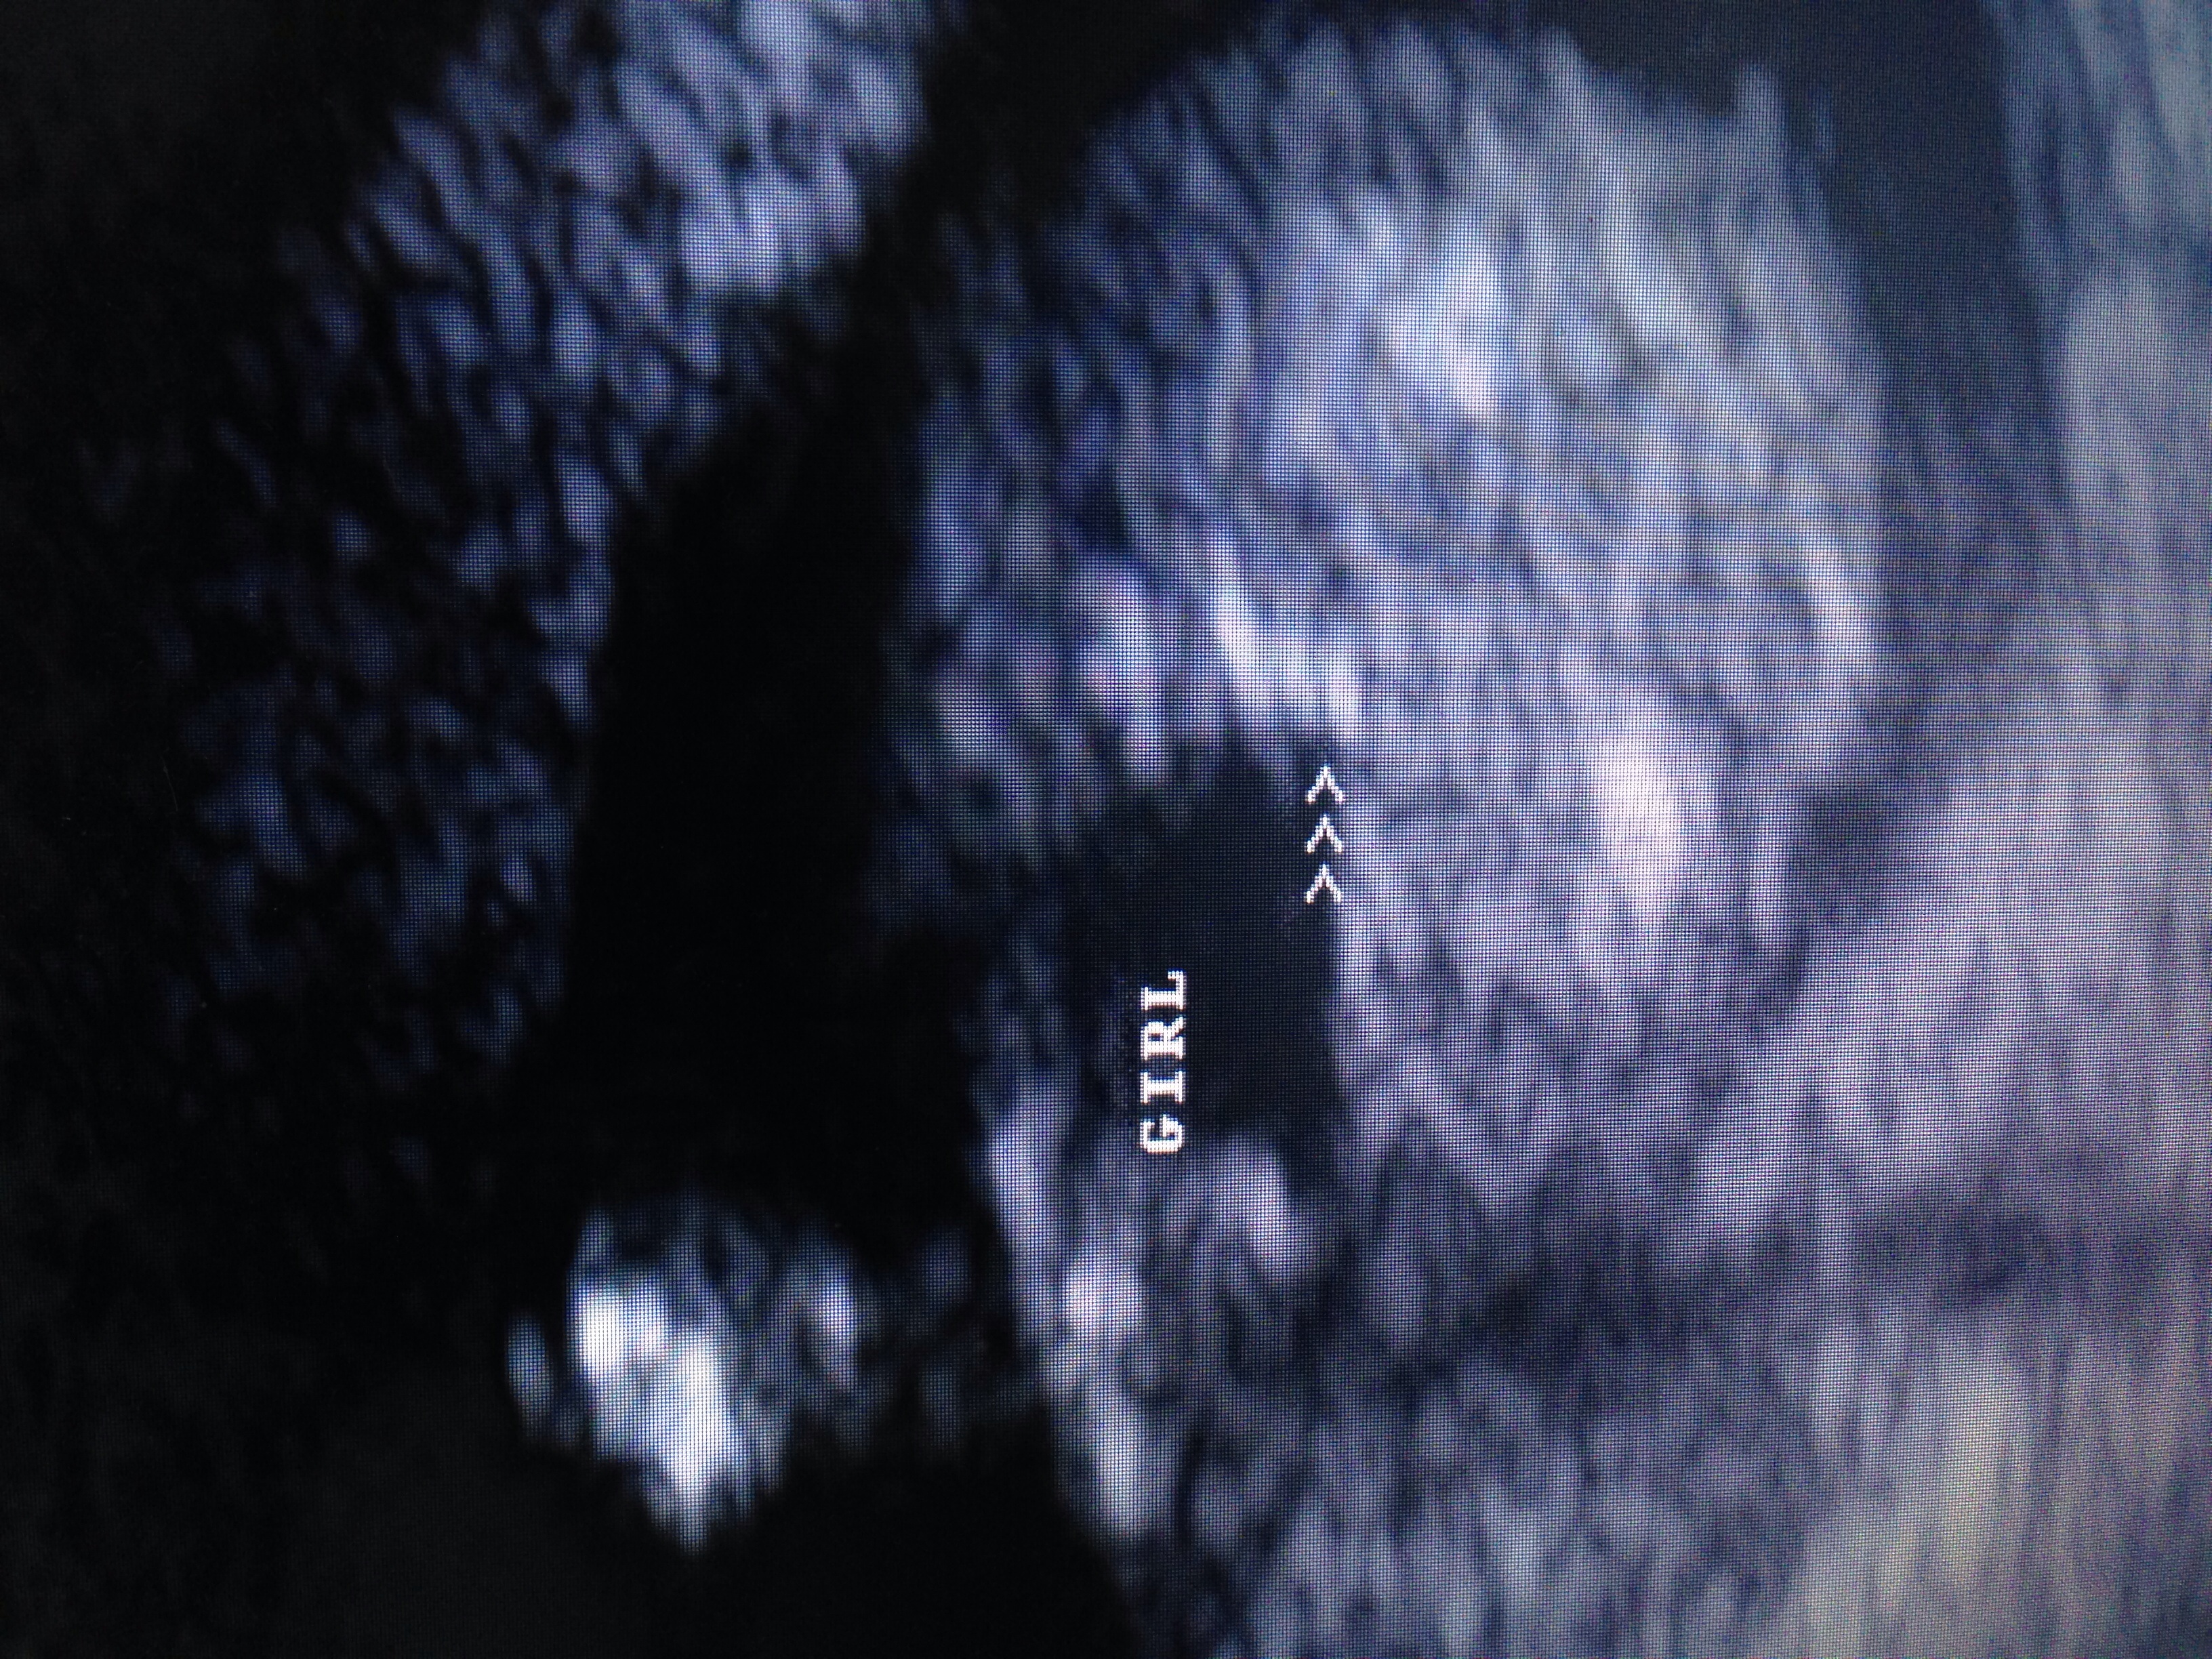

Attachment 17209Attachment 17210These pictures were taken at an elective ultrasound taken at 16 weeks. Baby kept her legs tucked but tech was able to get these 2 shots. Would you go out and buy pink or wait? Thank you in advance.

That looks totally girly to me :princess:

Huge congratulations on your daughter:HH:

Definitely girly, congrats! x

girl congrats

Girl for sure

Yeah, that is a girl. Those are good shots :) Congrats!!

Yep all girl!! Congrats :D